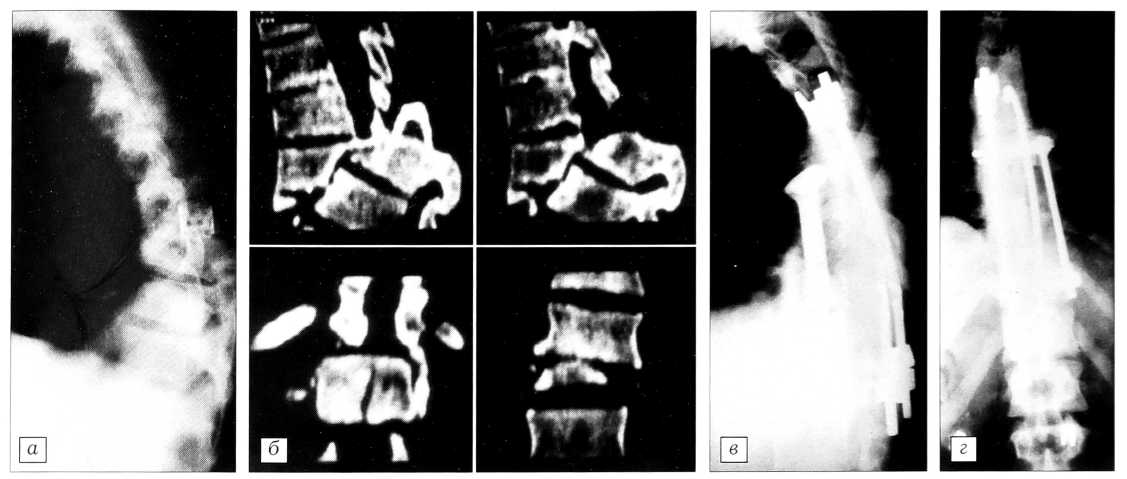

Рис. 2. Больная А. 47 лет. Солитарная миелома, патологический перелом тела Т12 позвонка со сдавлением эпиконуса спинного мозга, вялым нижним парапарезом, нарушением функции тазовых органов.

Боковая (а) и переднезадняя (б) спондилограммы, магнитно-резонансная томограмма нижнегрудного и поясничного отделов позвоночника (в) до оперативного лечения; боковая (г) и переднезадняя (д) спондилограммы после выполнения тотальной спондилэктомии Т12 позвонка, переднего спондилодеза T1l—L1 по типу полного замещения тела позвонка, задней внутренней транспедикулярной коррекции и фиксации позвоночника системой «Теnоr».